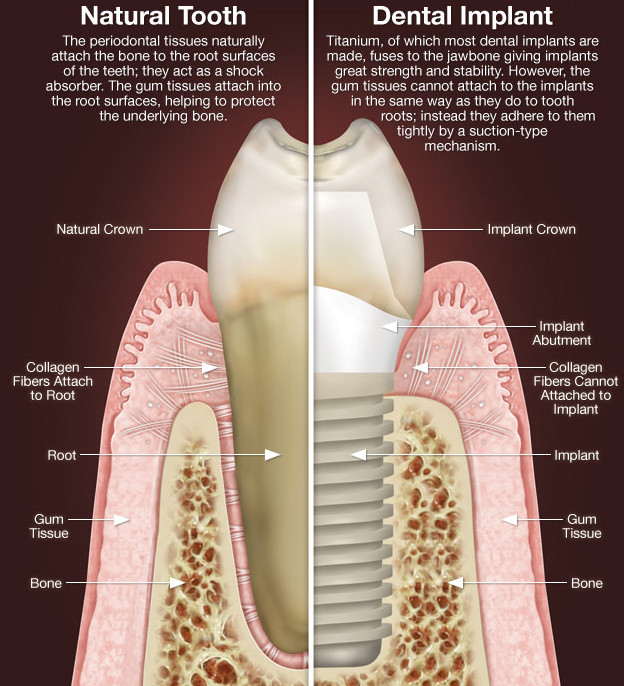

Do Dental Implants Really Mimic Natural Teeth?Healthy Body, Healthy …

Cosmetic Dentist in Greece Why do I recommend preserving natural teeth …

How dental implants work – Dental News Network

How do dental implants work? ⋆ Dental House

Dental Implants Portland OR | What Are Dental Implants